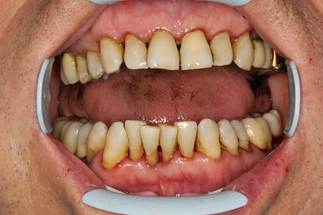

В основной группе 2 на фоне проводимого комплексного лечения с использованием геля «Метрогил-дента» отмечали улучшение как субъективных, так и объективных проявлений заболевания: уменьшались болезненность и кровоточивость десен, галитоз. Через 30 дней после лечения пациенты обеих групп отмечали значительное снижение болезненности, отека и кровоточивости десен, исчезновение неприятного запаха изо рта, некоторое снижение подвижности зубов, появление уверенности при жевании, улучшение общего состояния. При объективном обследовании отмечали уплотнение десневого края за счет уменьшения отека, существенное улучшение гигиенического состояния полости рта, прекращение выделения экссудата из пародонтальных карманов (Рисунок 13).

| до лечения | через 30 дней после лечения |

| Рисунок 13. Динамика состояния тканей пародонта у пациента с ХГП тяжелой степени через 30 дней после комплексного консервативного лечения с местным применением препарата «Метрогил-Дента» . | |